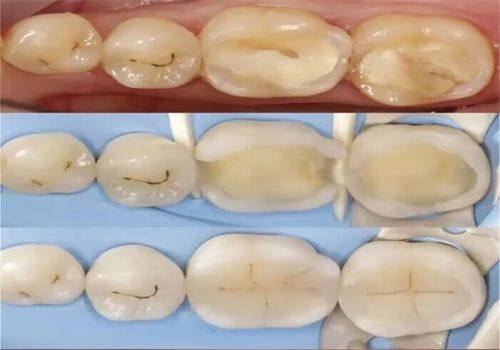

嵌体修复

当牙齿出现大面积缺损时,直接填充可能就不太合适了,这时就需要采用定制嵌体修复的方法。嵌体有金属嵌体、瓷嵌体等不同类型可供选择。医生会先为你的牙齿取模,然后根据模型定制出与你牙齿理想匹配的嵌体。

嵌体修复的好处可不少。它能更好地修复牙齿的形态和功能,让牙齿重新发挥正常的咀嚼作用。而且嵌体的边缘密合度非常高,就像给牙齿戴上了一个精细的“帽子”,可以大大减少继发龋发生的概率,延长牙齿的使用寿命。